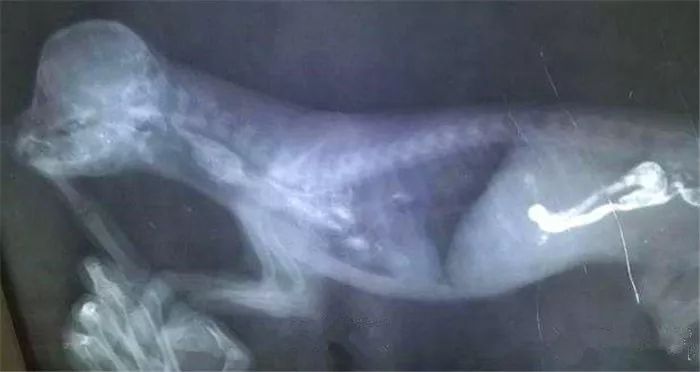

其次呢就是狗狗的身体构造其实和人是不一样的,学医的宝宝这时候就到了你们发挥的时候了,人的肠胃结果是曲折回环的,但是狗狗的肠道是笔直的,对的,就是传说中的直肠子。

所以当狗狗的肠道或者胃部受到刺激的时候,狗狗就会呕吐。

正常的呕吐是不会影响狗狗的健康的,但是多次的呕吐,往往意味肠道或者胃部出现病变,这是很危险的。